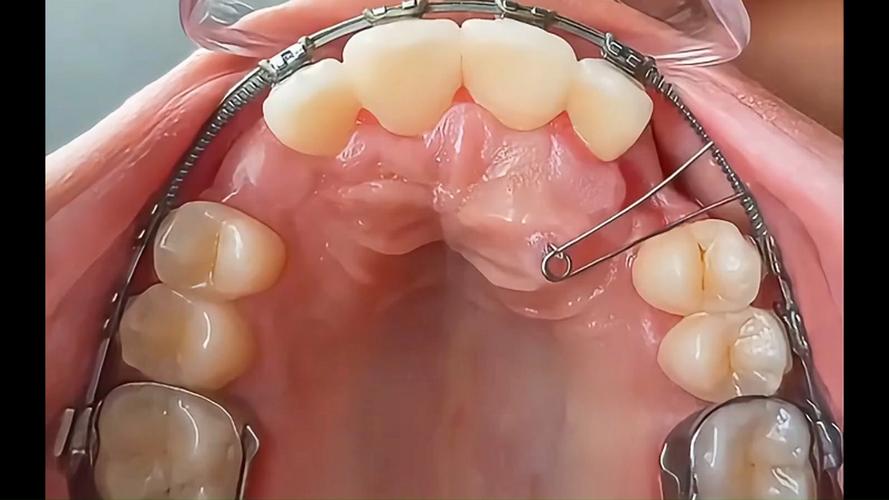

矫治装置选择与安装

- 口内装置:在上颌乳磨牙或前磨牙上粘带环,焊接牵引钩(通常在第一乳磨牙/第一前磨牙和第二乳磨牙/第二前磨牙之间),形成“牙弓支持”;部分患者需配合上颌活动矫治器或固定矫治器(如方丝弓矫治器),增强支抗。

- 口外牵引装置:常用“面具式前方牵引器”(由额托、颏托、牵引杆组成)或“头帽式前方牵引器”(头帽固定于头顶和枕部),牵引杆连接口内牵引钩,通过弹性橡皮圈或螺旋弹簧施加牵引力。